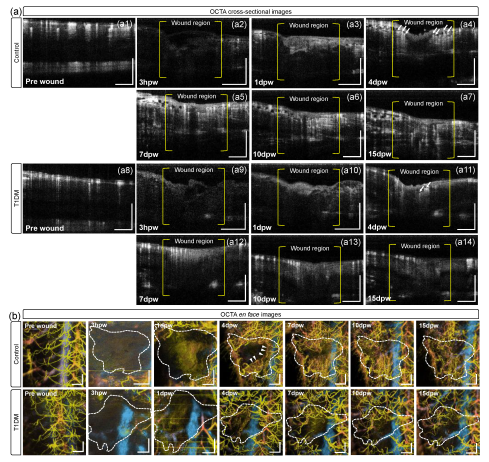

3.2. Structural Changes during Cutaneous Wound Healing